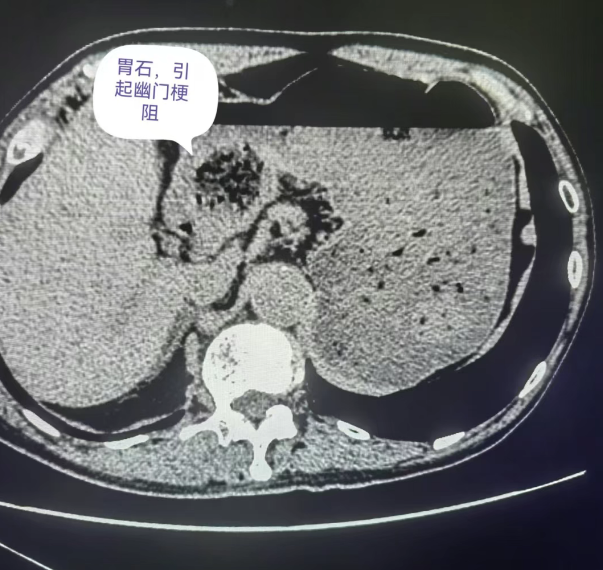

胃结石在初期可能没有明显症状,最多让人感觉有点上腹部不适或者饱胀,很容易被忽略。但随着它慢慢长大,就开始“兴风作浪”。腹痛是最常见的症状之一,疼痛程度不一样,有的是隐隐作痛,有的则是胀痛,甚至剧烈疼痛。还会出现恶心、呕吐的情况,要是结石损伤了胃黏膜,还可能引发呕血、黑便。更严重的,胃结石可能导致幽门梗阻,让食物无法正常通过,那可就麻烦大了。幽门梗阻发生时,食物和胃液无法顺利进入小肠进行消化和吸收,大量积聚在胃内,导致胃内压力升高,引发严重的呕吐。患者会频繁呕吐出大量酸臭的胃内容物,且呕吐后症状也难以缓解,还可能伴有脱水、电解质紊乱等严重并发症。

四、CT影像:胃结石的“个性画像”

在胃结石的 CT 影像中,不同类型的结石有着独特的“长相”。当胃内存在植物性结石时,其影像表现通常为形状不太规则的低密度影。仔细观察,能看到内部有散在分布的点、条状稍高密度影,这是植物纤维的影像特征。若是混合性结石,CT影像则更为复杂,既有低密度的植物成分区域,又有因钙化或其他矿物质沉积形成的高密度区域,密度不均匀,边界也相对模糊。例如:在一些长期存在的胃结石中,由于钙盐的不断沉积,结石内部会出现钙化灶,在CT影像上表现为高密度影,与周围低密度的植物成分形成鲜明对比。

而CT增强扫描在胃结石诊断中也有特殊意义。对于一些与胃壁关系密切、难以判断是否侵犯胃壁的结石,增强扫描能清晰显示胃壁各层结构。正常胃壁在增强后呈现均匀强化,若结石周围胃壁强化异常,如局部增厚、强化程度改变,就提示胃壁可能受到了结石的刺激或损伤,帮助医生更准确评估病情严重程度,为后续治疗方案的制定提供更可靠的依据。当胃壁受到结石刺激发生炎症时,在增强扫描图像上,炎症部位的胃壁会出现增厚、强化程度增加的表现,这表明该区域的血供增加,是炎症反应的典型特征。医生通过观察这些变化,可以判断胃壁炎症的范围和程度,从而选择合适的治疗方法,如是否需要使用抗生素进行抗感染治疗,或者是否需要及时进行手术干预。